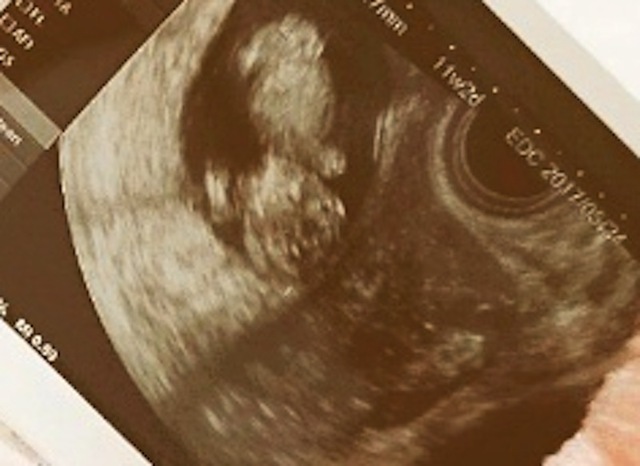

11週0日(11w0d・性別不明)|kiki34 さん(28歳)

エコー写真撮影時のエピソード:

両親や姉妹に報告するときにエコーの写真を見せました。とても喜んでもらえました。 毎回のエコー写真はアルバムにしてコメントをつけて保存するようにしています。

だんだん大きくなっているのが目に見えてわかりコメントを書くことによってその時の気持ちがわかるようになるので見返してて楽しいです。将来は産まれてきた我が子にあげる予定です!